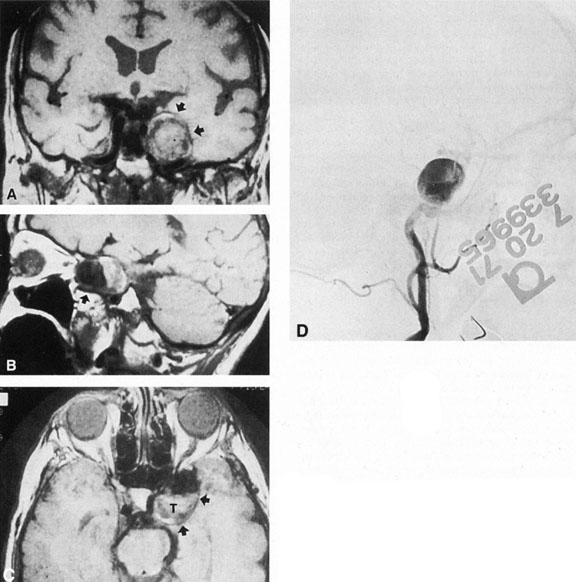

Fig. 3. Magnetic resonance images of intracavernous aneurysm in a 72-year-old woman with left retrobulbar pain and sixth-nerve palsy. A: Coronal section (TR, 800 ms; TE, 30 ms). B: Parasagittal section (TR, 1000 ms; TE, 20 ms). C: Axial section (TR, 800 ms; TE, 30 ms). Note partial occlusion by thrombus (T). D: In a similar patient, carotid arteriogram (subtracted, lateral view) demonstrates a large intracavernous aneurysm.

Intracavernous aneurysms are suspected by the clinical presentation of a chronic cavernous sinus syndrome and are diagnosed by enhanced computed tomography (CT), magnetic resonance imaging (MRI), and arteriography (see Fig. 3). Because of the location and configuration within the cavernous sinus, direct surgical approaches to cavernous carotid aneurysms are hazardous. In recent years intravascular occlusion of the internal carotid by detachable balloon has evolved as a safe and successful procedure, often with relief of pain and improvement in ophthalmoplegia.10 Unfortunately, these balloons are commercially unavailable at the time of this writing.

Fig. 4. Giant suprasellar (supraclinoidal) aneurysms. A: Carotid arteriogram (lateral view) shows a huge aneurysm of the internal carotid artery in a 59-year-old woman with progressing visual loss. Coronal (B) and axial (C) magnetic resonance imaging sections of a similar case. Note partial thrombus formation (TR, 2100 ms; TE, 80 ms).